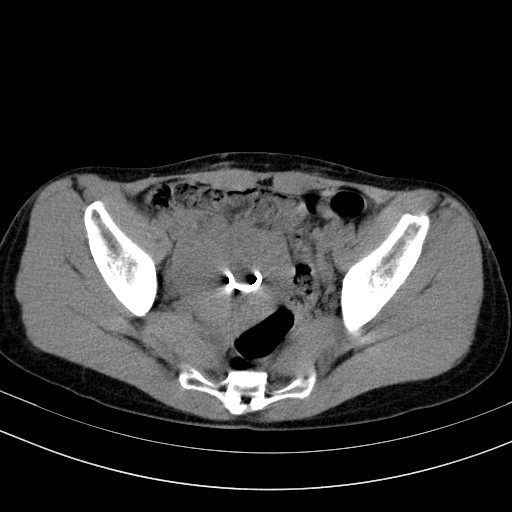

以下是引用随光逐影在2009-4-7 8:17:00的发言:[br]考虑宫颈占位性病变(宫颈癌?);建议行进一步检查。

以下是引用jiangjing在2009-4-7 16:46:00的发言:[br]宫颈增大,结构不清,右侧附件区可疑囊样占位,建议增强及mri 检查